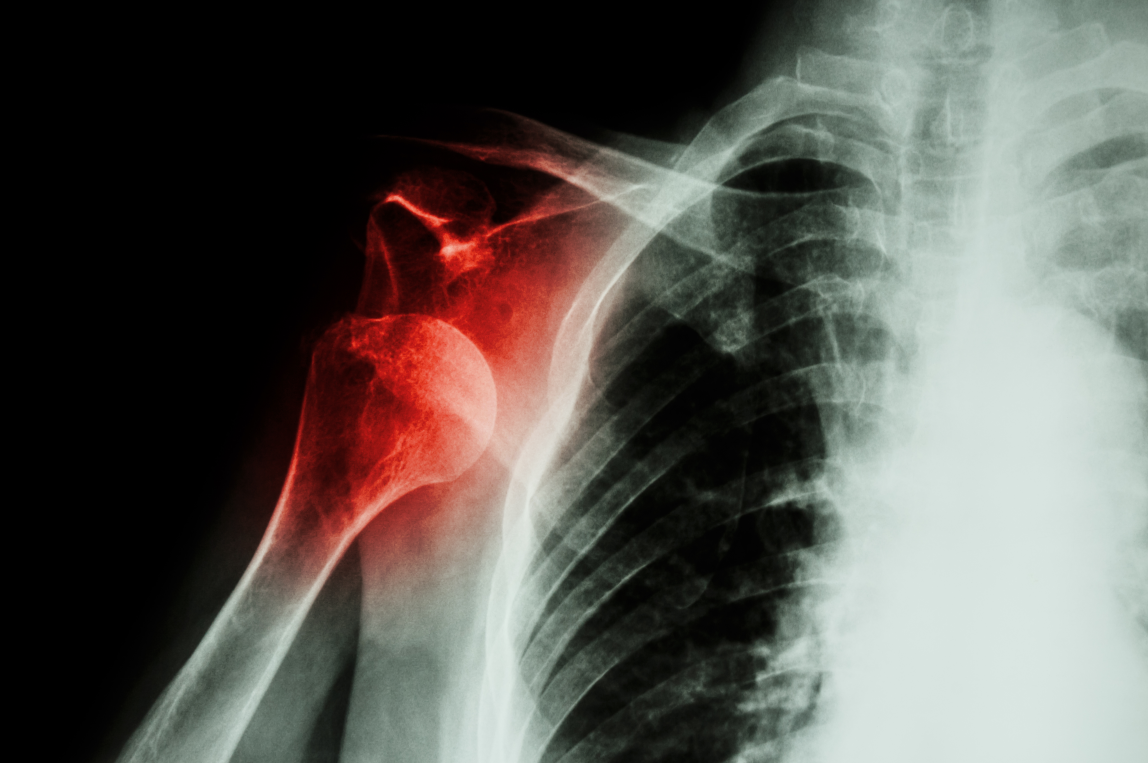

#肩关节骨折

老年骨质疏松性肩关节周围骨折诊疗中国专家共识(2023版)要点速览!

肩峰骨折是一种临床非常少见的骨折类型,指肩胛骨外侧与肱骨形成关节突出的部分出现的骨折,多由于直接暴力引起。